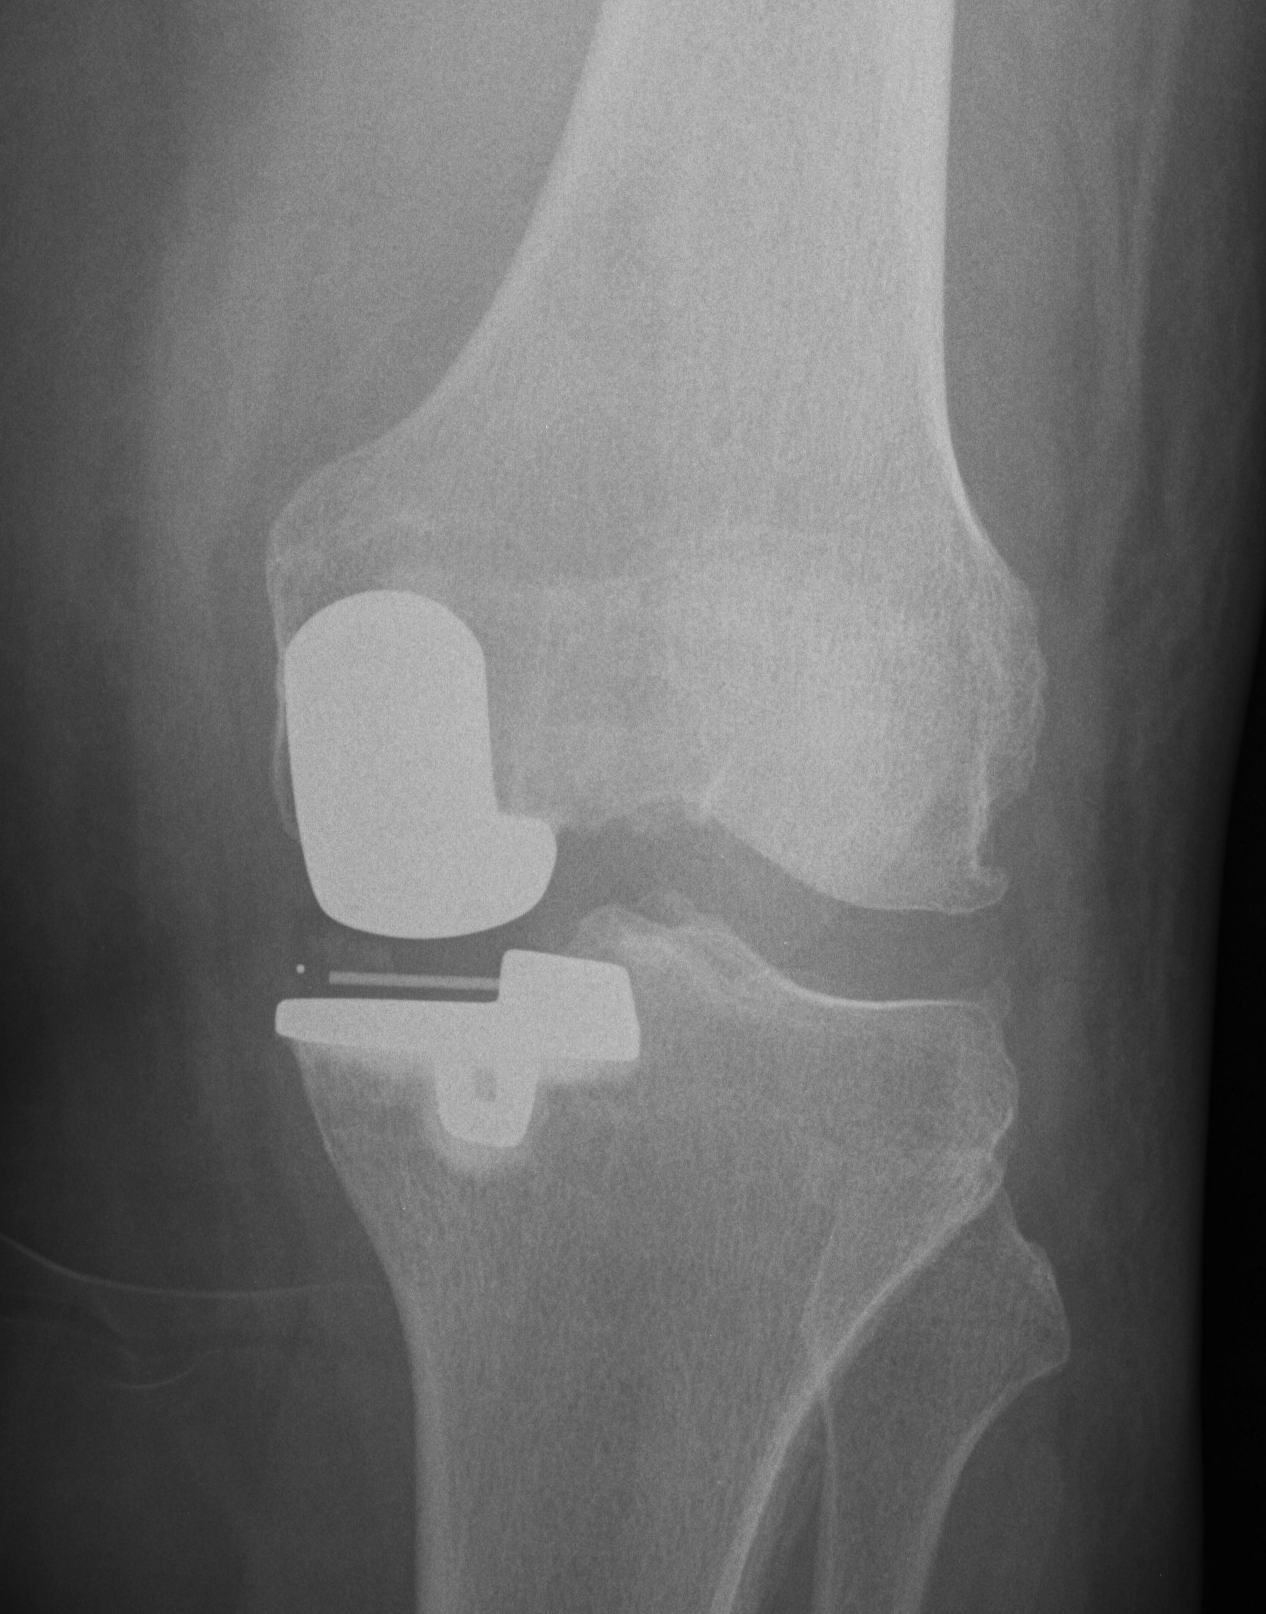

Patella Resurfacing

Options

1. Always resurface

2. Never resurface

3. Selectively resurface

Decision Making

Controversial

- literature divided on issue

Historically

- poor outcomes due to poor implant design

- now improved designs

- non resurfacing also improved due to better design and improved techniques in regard to tracking and rotation